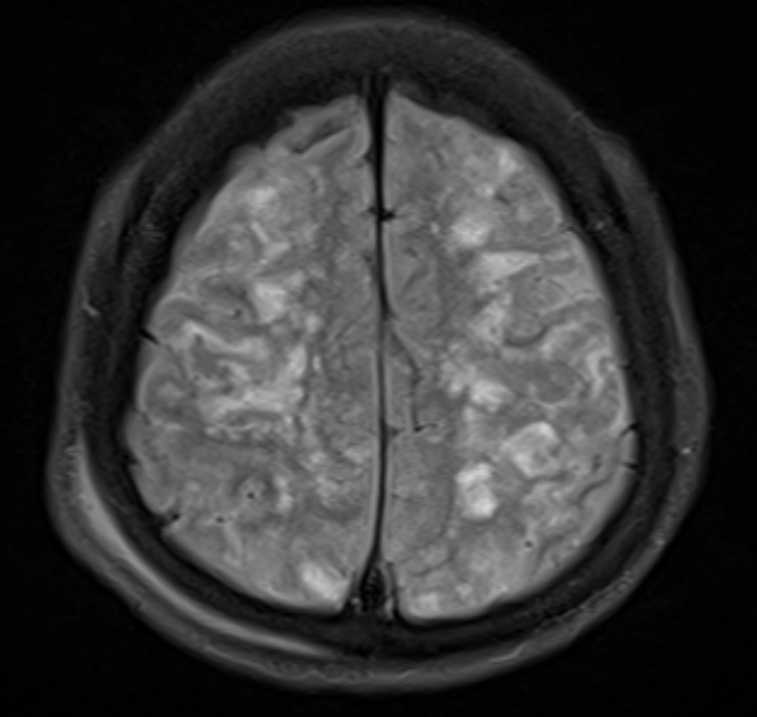

2)T2/FLAIR에서 미세출혈 및 부종 소견

· T2 및 FLAIR에서 뇌부종 소견이 관찰됨.

· 특히 기저핵(basal ganglia), 피질하백질(subcortical white matter), 시상(thalamus)에 병변이 잘 나타남.

· 일부 환자에서는 FLAIR에서 점상출혈이 보일 수 있음.